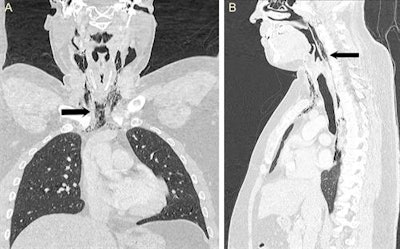

A lateral soft-tissue neck radiograph was performed, followed by an urgent, contrast-enhanced CT of the neck and thorax that confirmed the presence of extensive soft-tissue emphysema and pneumomediastinum.

"CT scan of the neck and thorax with water-soluble contrast swallow should be used as the gold-standard investigation, which can confirm the diagnosis and defines the exact pathological site," they wrote. "In addition, the normal CT appearance of the lung parenchyma and esophagus helps to exclude more serious causes of pneumomediastinum such as tracheobronchial rupture and Boerhaave's syndrome."